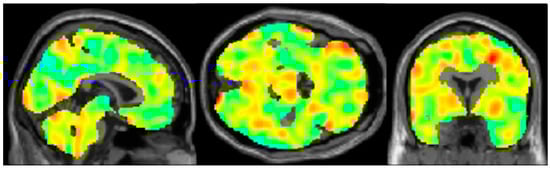

Do Epilepsy Patients with Cognitive Impairment Have Alzheimer’s Disease-like Brain Metabolism?

- Katako, A.; Shelton, P.; Goertzen, A.L.; Levin, D.; Bybel, B.; Aljuaid, M.; Yoon, H.J.; Kang, D.Y.; Kim, S.M.; Lee, C.S.; et al. Machine learning identified an Alzheimer’s disease-related FDG-PET pattern which is also expressed in Lewy body dementia and Parkinson’s disease dementia. Sci. Rep. 2018, 8, 13236. [Google Scholar] [CrossRef] [PubMed]

- Lau, A.; Beheshti, I.; Modirrousta, M.; Kolesar, T.A.; Goertzen, A.L.; Ko, J.H. Alzheimer’s Disease-Related Metabolic Pattern in Diverse Forms of Neurodegenerative Diseases. Diagnostics 2021, 11, 2023. [Google Scholar] [CrossRef] [PubMed]